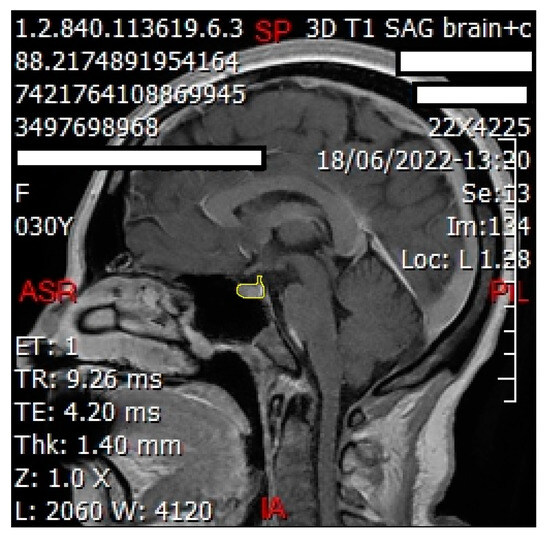

2.6. Grayscale Measurement

We employed ImageJ Fiji Software (Version 1.53q) to quantify the grayscale intensities of both the pituitary gland and the pons. After verifying sagittal sections containing the pituitary gland (Figure 2 and Figure 3) with a certified radiologist, we delineated its borders using the ‘Freehand Selections’ tool. Within the ‘Analyze’ tab, histograms were generated for each section, providing mean and standard deviation values of grayscale intensities. Using SPSS 25 (Statistical Package for the Social Sciences, IBM, Armonk, NY, USA), we calculated the overall mean and standard deviation across all sections for both the pituitary gland and the pons (mean and standard deviation from each section). The same methodology was applied to analyze the grayscale intensities of the pons (Figure 4 and Figure 5), ensuring consistency for normalization purposes. The normalized grayscale intensity was determined by dividing the mean grayscale intensity across all sections of the pituitary gland by that of the pons.

Figure 2. Sagittal cut of the brain showing delineation of the pituitary gland (shown in yellow line) to obtain the grayscale using ImageJ Fiji Software. This technique was performed for each sagittal cut involving the pituitary gland for each patient.